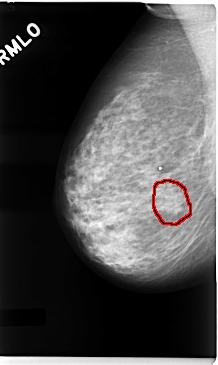

FILE: C_0041_1.RIGHT_MLO.OVERLAY

TOTAL_ABNORMALITIES 1

ABNORMALITY 1

LESION_TYPE MASS SHAPE IRREGULAR MARGINS SPICULATED

ASSESSMENT 4

SUBTLETY 3

PATHOLOGY MALIGNANT

TOTAL_OUTLINES 1

BOUNDARY